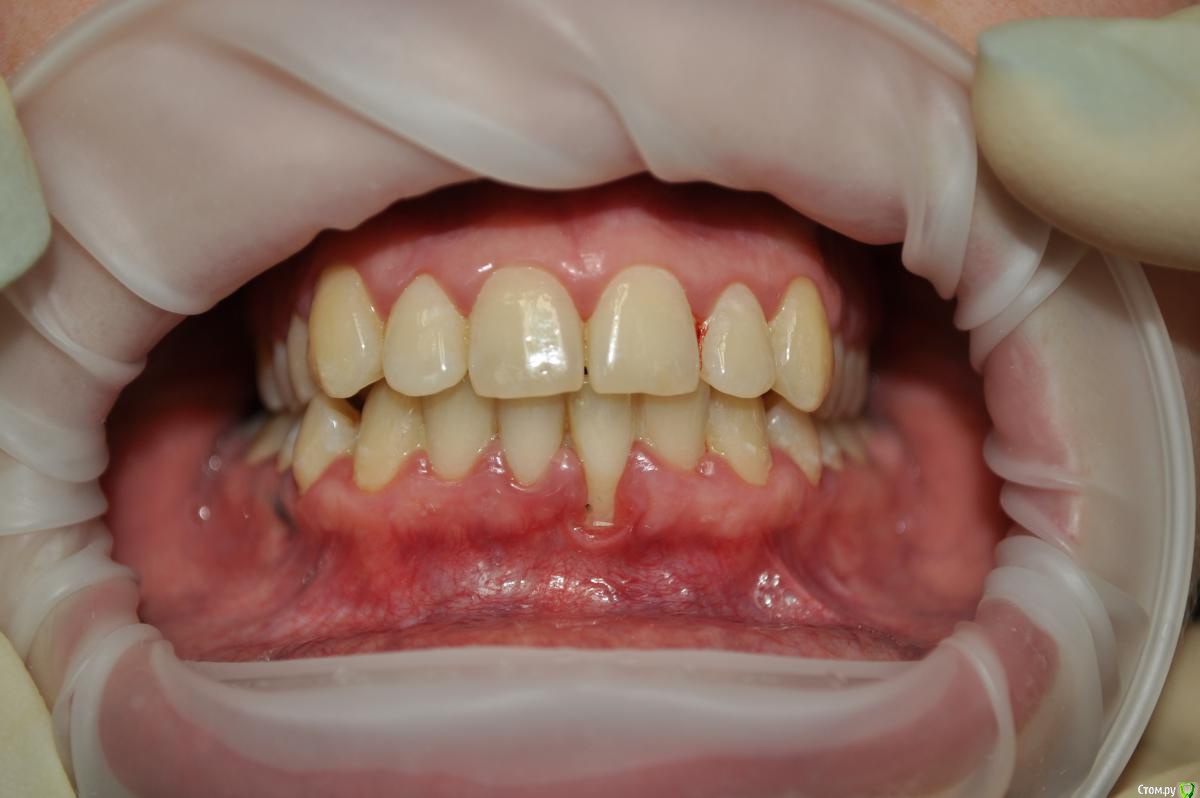

IshIm0 Опубликовано 1 апреля, 2016 Поделиться Опубликовано 1 апреля, 2016 Добрый день коллеги. Девочке 24 года, 1.5 года после ортодонтического лечения, пол года назад заметила рецессию. Как я думаю: 1 этап - вестибулопластика. 2 этап - через пол года забор сст с неба и устранение рецессии. Восьмерку кстати тоже удалять нужно. Поделитесь своим ви'дением этой ситуации, советами, "подводными камнями" ) Все ли верно по срокам? Ссылка на комментарий

Acidrocker Опубликовано 2 апреля, 2016 Поделиться Опубликовано 2 апреля, 2016 прикрепленки рядом много, порекомендовал бы латерально-смещенный лоскут. 6 Ссылка на комментарий

Доктор Добрых Дел Опубликовано 2 апреля, 2016 Поделиться Опубликовано 2 апреля, 2016 В чем причина данной рецессии? отсутствие вестибулярной кости. Ссылка на комментарий

zzkz Опубликовано 6 апреля, 2016 Поделиться Опубликовано 6 апреля, 2016 отсутствие вестибулярной кости.Её может не было изначально. Ортодонтия спровоцировала. Тож за латеральный лоскут Ссылка на комментарий

dr.moskvichev Опубликовано 7 апреля, 2016 Поделиться Опубликовано 7 апреля, 2016 Закрыть рецессию классическим коронарно-смещенным лоскутом+сст. Преддверие углубить можно и позже при необходимости 1 Ссылка на комментарий